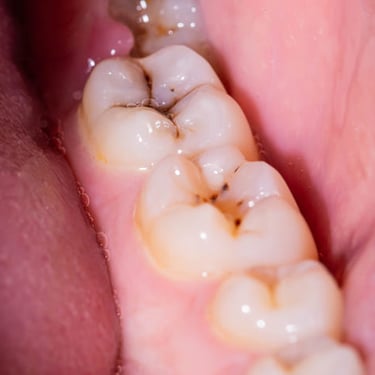

Caries Radicular

La caries radicular es la descomposición del cemento y la dentina en la raíz del diente, común en personas mayores con recesión gingival.

Los pacientes pueden experimentar sensibilidad y dolor en la raíz expuesta.

El tratamiento incluye la eliminación de la caries y la restauración de la raíz. La prevención incluye una buena higiene oral y el uso de flúor.